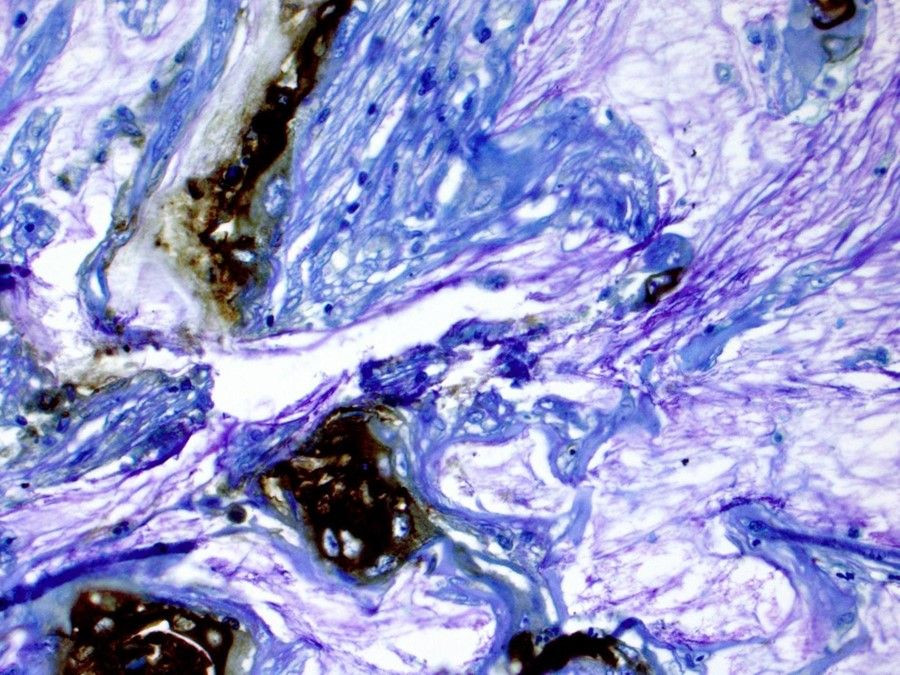

Un inhibidor de PARP reduce los tumores en pacientes con cáncer de páncreas con mutaciones

Más de dos tercios de los pacientes con cáncer de páncreas que albergan mutaciones genéticas vieron cómo su tumor dejaba de crecer o se reducía sustancialmente después de que se les cambiara la quimioterapia intensiva por el inhibidor de PARP rucaparib como terapia de mantenimiento, según informan en línea investigadores del Centro Oncológico Abramson (ACC) de la Universidad de Pensilvania en el `Journal of Clinical Oncology`.

Los resultados del ensayo de fase II del ACC respaldan el uso de rucaparib en pacientes con cáncer de páncreas con variantes BRCA1, BRCA2 y PALB2 para ayudar a controlar el crecimiento del tumor sin los agresivos efectos secundarios de la quimioterapia.